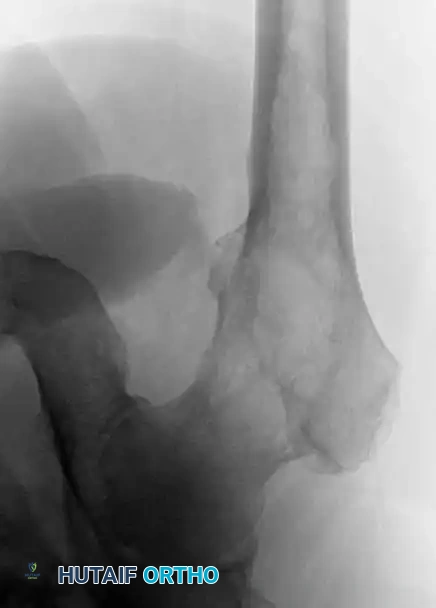

Image

Anteroposterior and lateral radiographs of the proximal femur of a 61-year-old man with multiple myeloma showing multiple lytic lesions.